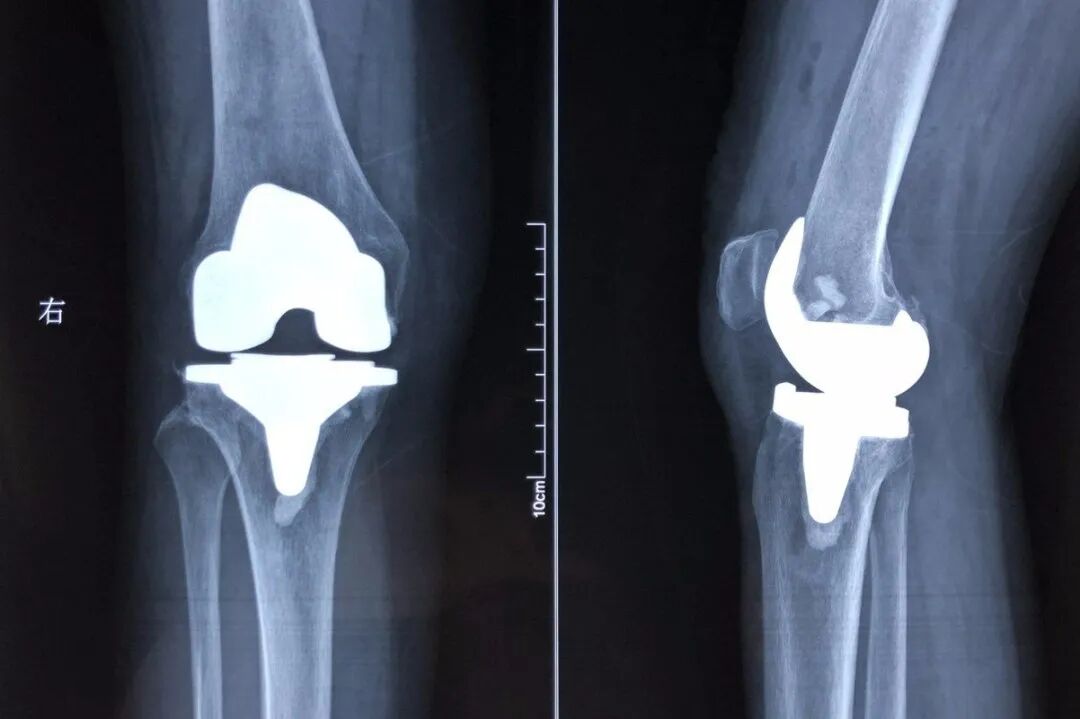

关节炎绝对是难缠的病,得上后关节肿、痛、积液、僵直、增生、骨刺、活动艰难,甚至就此残废!让人痛不欲生,难怪常被称为“不死的癌症”!相信很多人都被爷爷奶奶的“老寒腿”现身说法过!认为不好好保暖就会得“老寒腿”(骨关节炎)!事实真是这样吗?其实不然,关节炎的发病危险因素有很多,年龄的增长、体重超标、关节损伤、雌激素缺乏、过度运动、遗传因素、特殊职业人群、吸烟、维生素D缺乏等等那为什么膝盖会因为一变天就跟着疼?虽然骨关节炎与温度无甚关系,但是寒冷却会诱发关节炎的发作。低温情况下,关节液的减少,粘度变稠、关节附近肌肉和微小血管的收缩等都会令关节不适、僵硬,疼痛更加明显。除此之外,阴雨天容易让人产生负面情绪,对痛感的敏感性也大大提高了。2.激素:治标不治本,长期用还会骨质疏松,股骨头坏死。5.关节置换手术:也就是换一个人造关节。而换过关节的人都清楚,手术不但创伤大,风险高,并发症多,而且换过之后的关节自己根本就不想用,换过的关节日久还会出现部件松动磨损,有一定的使用寿命。目前,传统医学无法对骨关节炎进行根治,只能通过传统方式来有效控制症状,改善关节功能。但是医学是不断发展的,随着干细胞治疗疾病机理的研究,干细胞综合治疗方案在关节炎领域展现了不错的治疗效果吕女士今年69岁,6年前开始出现双侧膝关节疼痛、僵硬等症状,逐渐加重,右侧更加严重。到2022年2月份,出现需要拄拐杖行走的情况,最多只能走100米,上下楼行动困难,需要拽着栏杆一步步挪动,不能坐低矮的凳子,膝关节处于这个位置时严重疼痛,而且坐下时间太久也站不起来。医生建议早些做人工膝关节置换手术,但吕女士有糖尿病、高血压等慢性基础病,手术风险会增加。而且吕女士自身对手术有恐惧心理,因此心里面一直拒绝手术治疗。一直通过保守治疗的办法来改善疼痛,但后来逐渐没有了效果。2022年4月,吕女士的儿子在朋友的介绍下,通过回输干细胞的方式来改善关节炎,且在治疗过程中,不会让患者很痛苦。专家与其在进行了沟通和了解后,为吕女士制定了干细胞回输的方案。第一次回输完后,左侧膝关节疼痛、僵硬明显减轻。三次干细胞回输完之后,左侧膝关节基本上没有了疼痛和僵硬的感觉。右侧膝关节疼痛程度减轻了60%,僵硬也减轻了,关节活动度增大,可进行小幅度缓慢下蹲。且上下楼的过程中,膝盖不再感到疼痛,可中长段距离行走。三次干细胞的回输,让吕女士的疼痛得到可观的改善,且日常生活的质量也得到提高,而且也很少出现因为关节疼痛而导致情绪变差的情况。